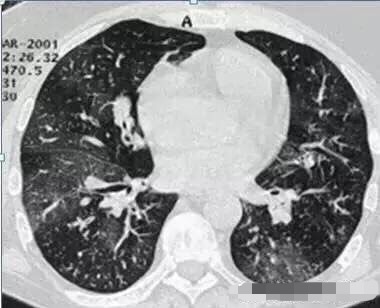

2. 那么,王大夫,这个磨玻璃影那么多,是不是也是肺癌呢?

呵呵,这个也不是啦,这个叫马赛克灌注,是肺内通气灌注不一致的表现,主要是小支气管炎症,导致肺内局部积气,像马赛克拼图一样。不是肺癌,当然不用担心啦。